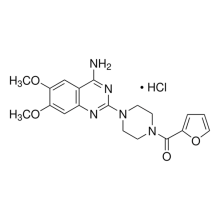

Our expertise in biological and chemical systems

Our products

Discover our products